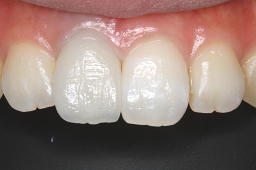

症例写真 セラミック治療前後

・ 白い歯を保ちたい!

・ 治療後の歯を目立たなくしたい!